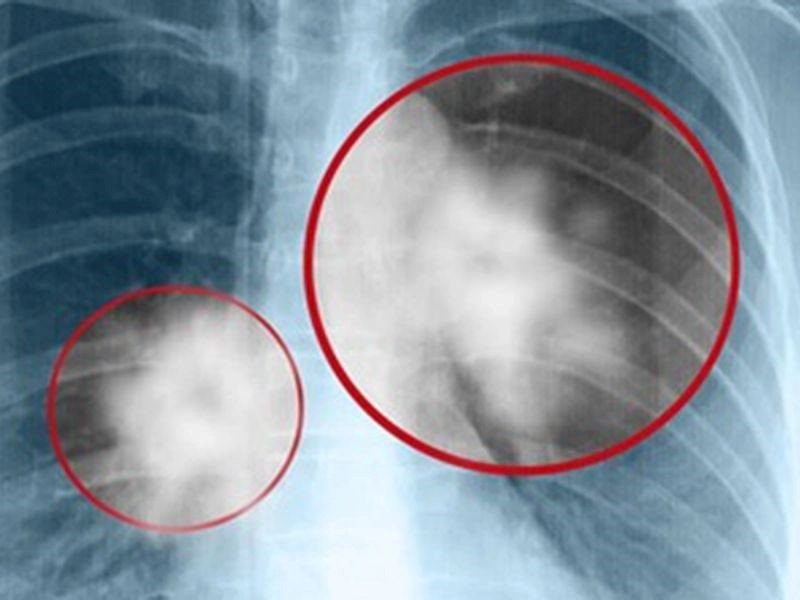

Ung thư phổi khi di căn xương là hiện tượng các tế bào ung thư từ khối u phổi di chuyển đến các mô xương qua máu hoặc hệ bạch huyết. Xương là một trong ba vị trí di căn thường gặp nhất trong ung thư phổi, chỉ sau gan và tuyến thượng thận, với khoảng 30%-40% bệnh nhân ung thư phổi giai đoạn cuối bị ảnh hưởng. Mặc dù ung thư phổi di căn xương không thể điều trị triệt để, vẫn có các liệu pháp giúp kéo dài tuổi thọ và cải thiện chất lượng cuộc sống cho người bệnh.

Ung thư phổi di căn xương là giai đoạn mấy? Theo các nghiên cứu trên tạp chí về điều trị ung thư, ung thư phổi di căn xương thường ảnh hưởng đến các khu vực như cột sống, xương sườn, xương chậu, xương đùi, xương cánh tay trên, xương bả vai và xương ức. Ngoài ra, nó cũng có khả năng lan đến xương ở bàn tay và bàn chân, gây đau đớn và hạn chế vận động.